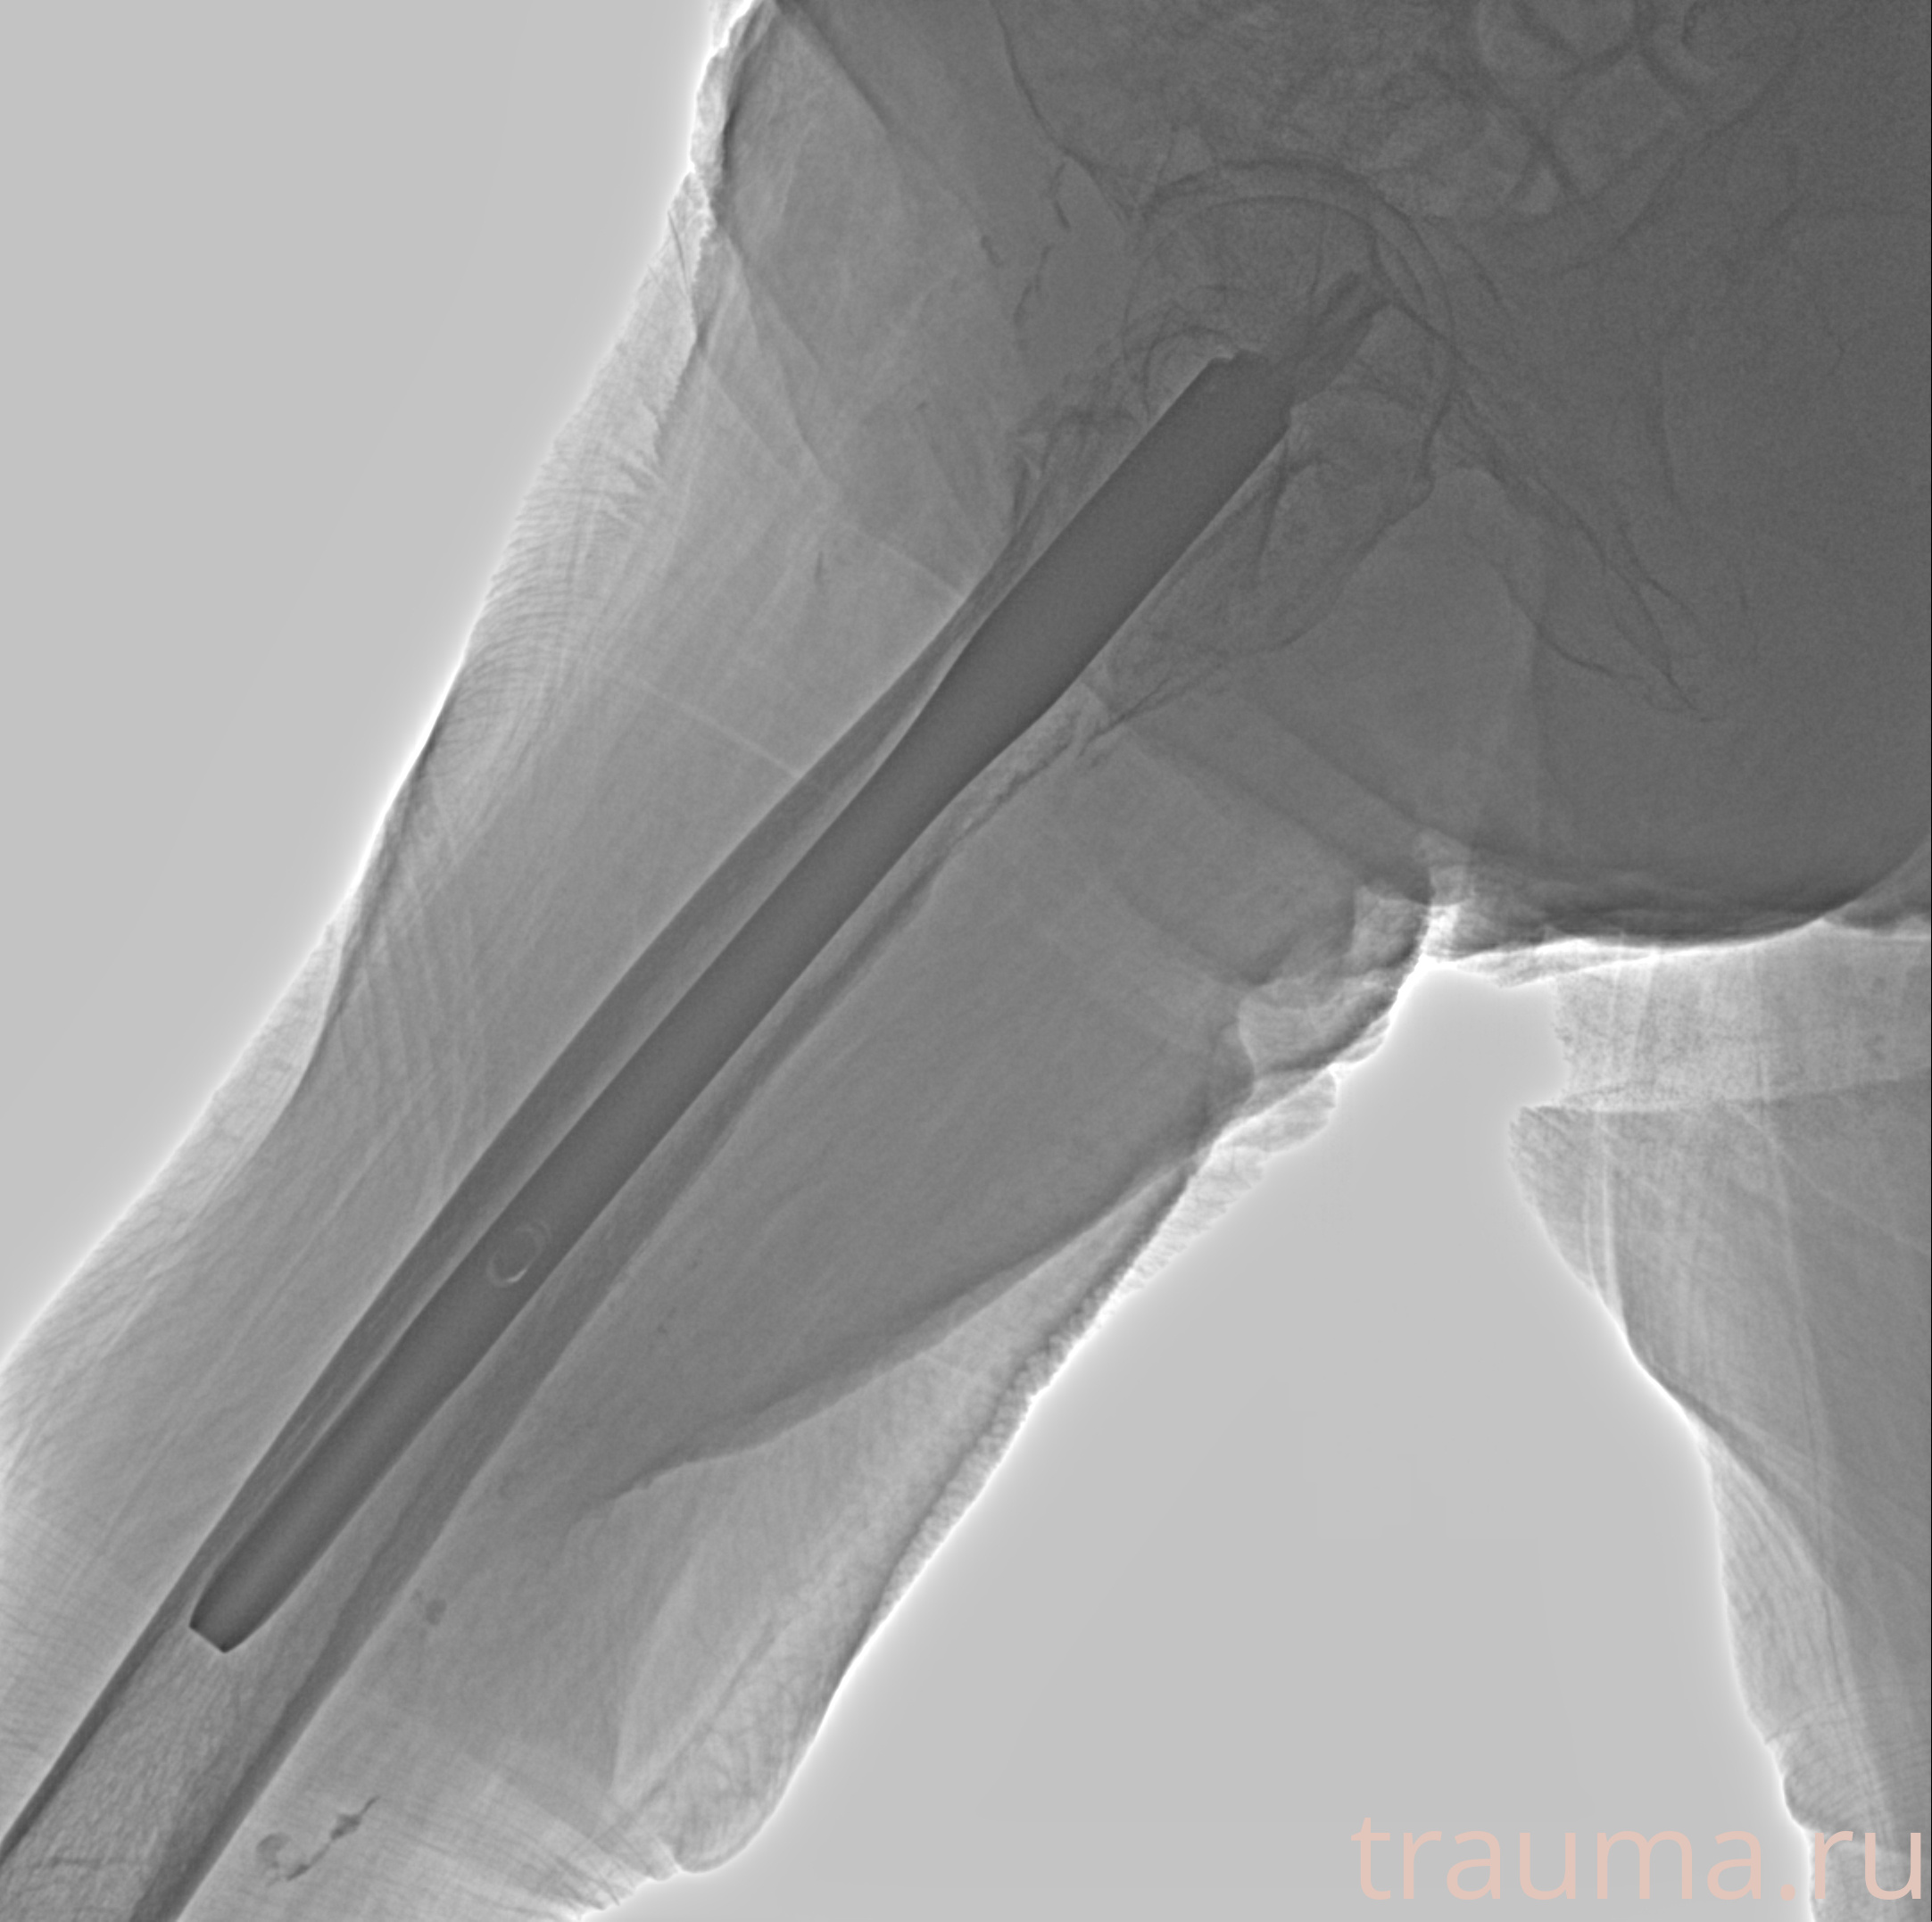

Рентгенограммы

Рентген на дому: по вашему адресу приезжает врач-рентгенолог, травматолог-ортопед с мобильным рентгеновским аппаратом, проводит диагностику травмы или заболевания, делает необходимые рентгенограммы, дает рекомендации по дальнейшему лечению. Получить качественные снимки в домашних условиях возможно благодаря уникальной методике, разработанной МосРентген Центром для института  Склифосовского

при переломе шейки бедра и пневмонии от компании МосРентген Центр - партнера Института имени Склифосовского